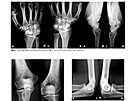

Neobvyklý úraz a jeho léčbu popsal primář v odborném časopise. Neobvyklý úraz a jeho léčbu popsal primář v odborném časopise. Neobvyklý úraz a jeho léčbu popsal primář v odborném časopise. Neobvyklý úraz a jeho léčbu popsal primář v odborném časopise. Pod vedením primáře Jaroslava Pilného se novoměstským specialistům povedla...